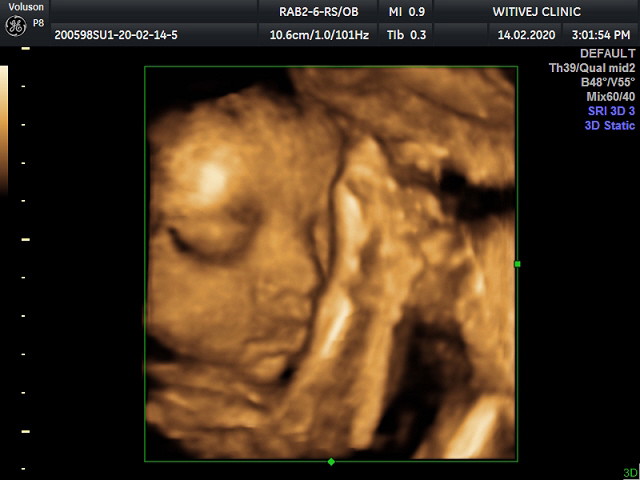

ซาวน์ 4 มิติ 25week เพศหญิง

25w5d น้องเอามือปิดหน้า กำหนดคลอด 20 พ.ค. จ้า 👶🏻

ซาวด์ตอน 29+5 ปัจจุบัน 31+5 ได้ลูกสาว ผ่า16เมษาค่ะ

สาวเหมือนกันค่ะ32+3w ค่ะกำหนดคลอด21เมค่า

34+2w 8เมษา ผู้หญิงเหมือนกันคะ